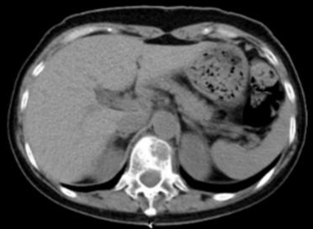

案例2:

胰腺癌引起的腹痛患者,男性,65岁,确诊为晚期胰腺癌,疼痛剧烈,体位受影响,喜欢呈大虾一样蜷缩状,影响睡眠和日常活动。尽管使用了阿片类药物,但疼痛控制仍不理想。给予CT引导下腹腔神经丛神经毁损术后,患者的疼痛评分从8分降至3分,阿片类药物的使用量减少50%,生活质量显著提高(图2)。

图2:CT引导下腹腔神经丛毁损术